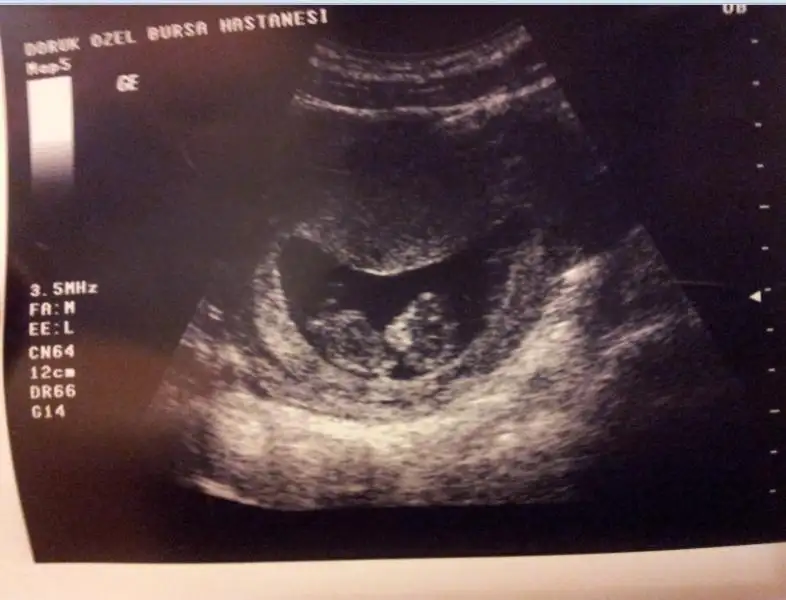

12 haftaliik benm bebisim canm dun doktrum kiz oldugunu soyledi ikinci kizim geliyo saglikla gelsinler ins busene kiz senesi galibaCanm bence senin bebisin kiz belli olunca haber verirsn nasilmis bebisin iyimi bnde resim koyucaktim ama nubu hic belli degil tlfdan koyamafimda[/QUOTE

12 haftaliik benm bebisim canm dun doktrum kiz oldugunu soyledi ikinci kizim geliyo saglikla gelsinler ins busene kiz senesi galiba